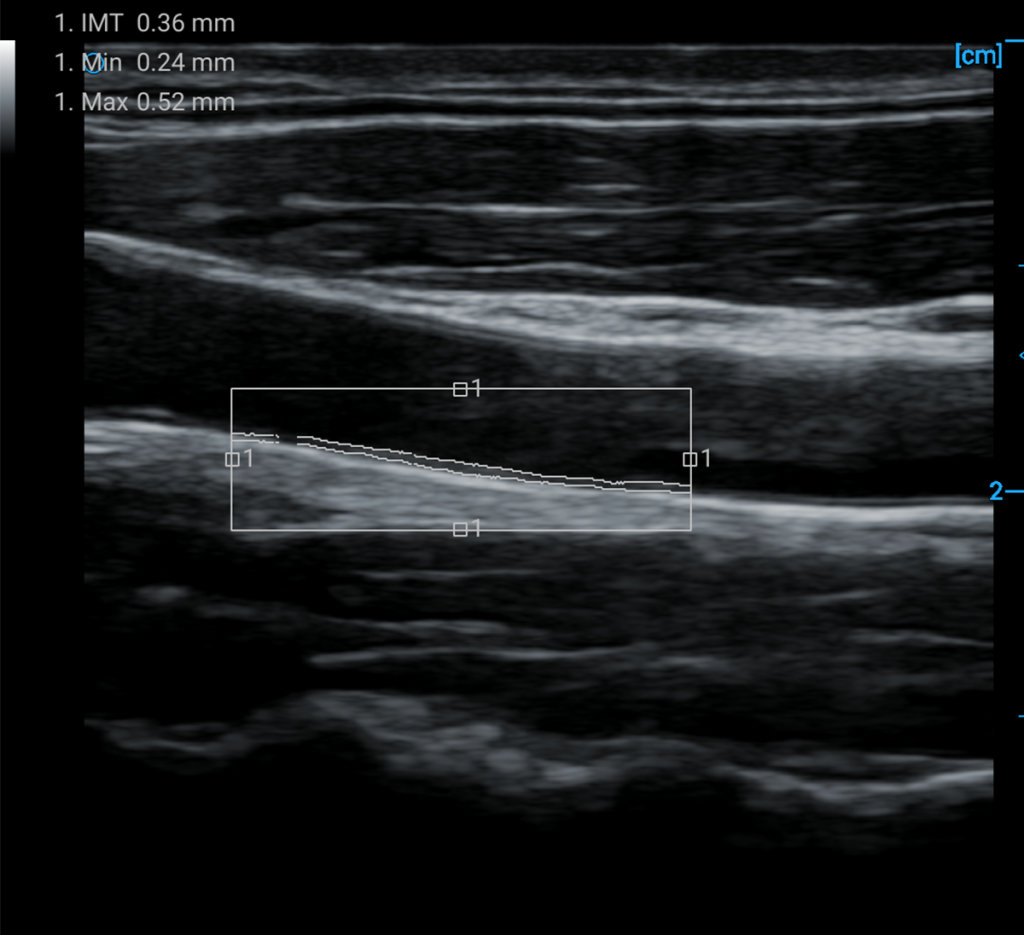

IMT automatic measurement and calculation